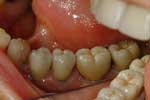

Riabilitazione parziale fissa su impianti

Caso iniziale

Particolare del lato destro